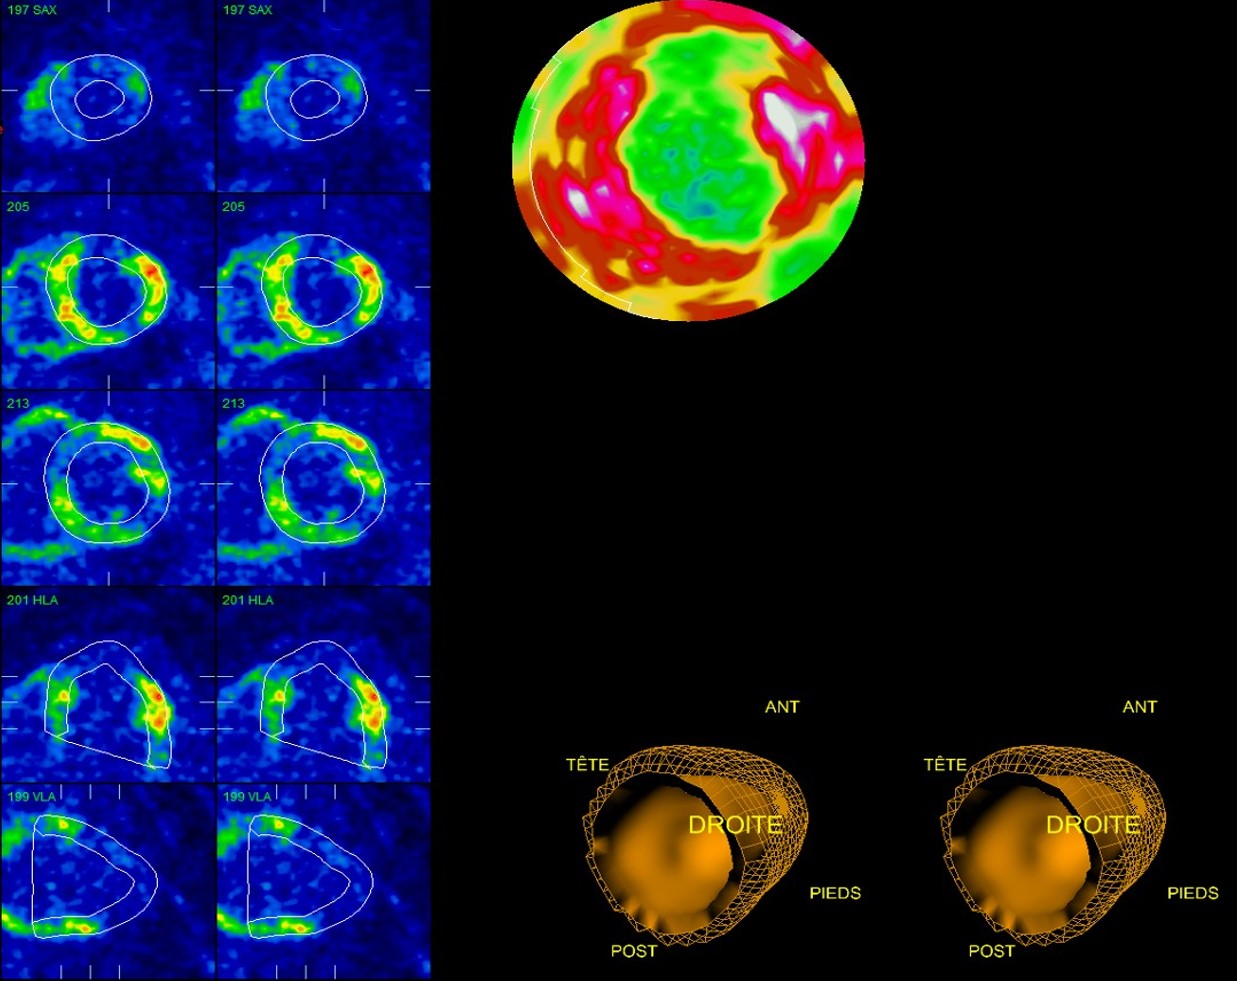

Scintigraphie au 99mTc-MIBI repos et persantine seule :

Hypoactivité septale, inférieure et antéro-latéro médiane.

Discrètement améliorée sur les clichés à la persantine seule.

Doute entre atteinte granulomateuse ou fibrose cardiaque

Lésion granulomateuse septale, inférieure et antéro-latérale concordante avec les lésions hypofixantes scintigraphie au 99mTc-MIBI